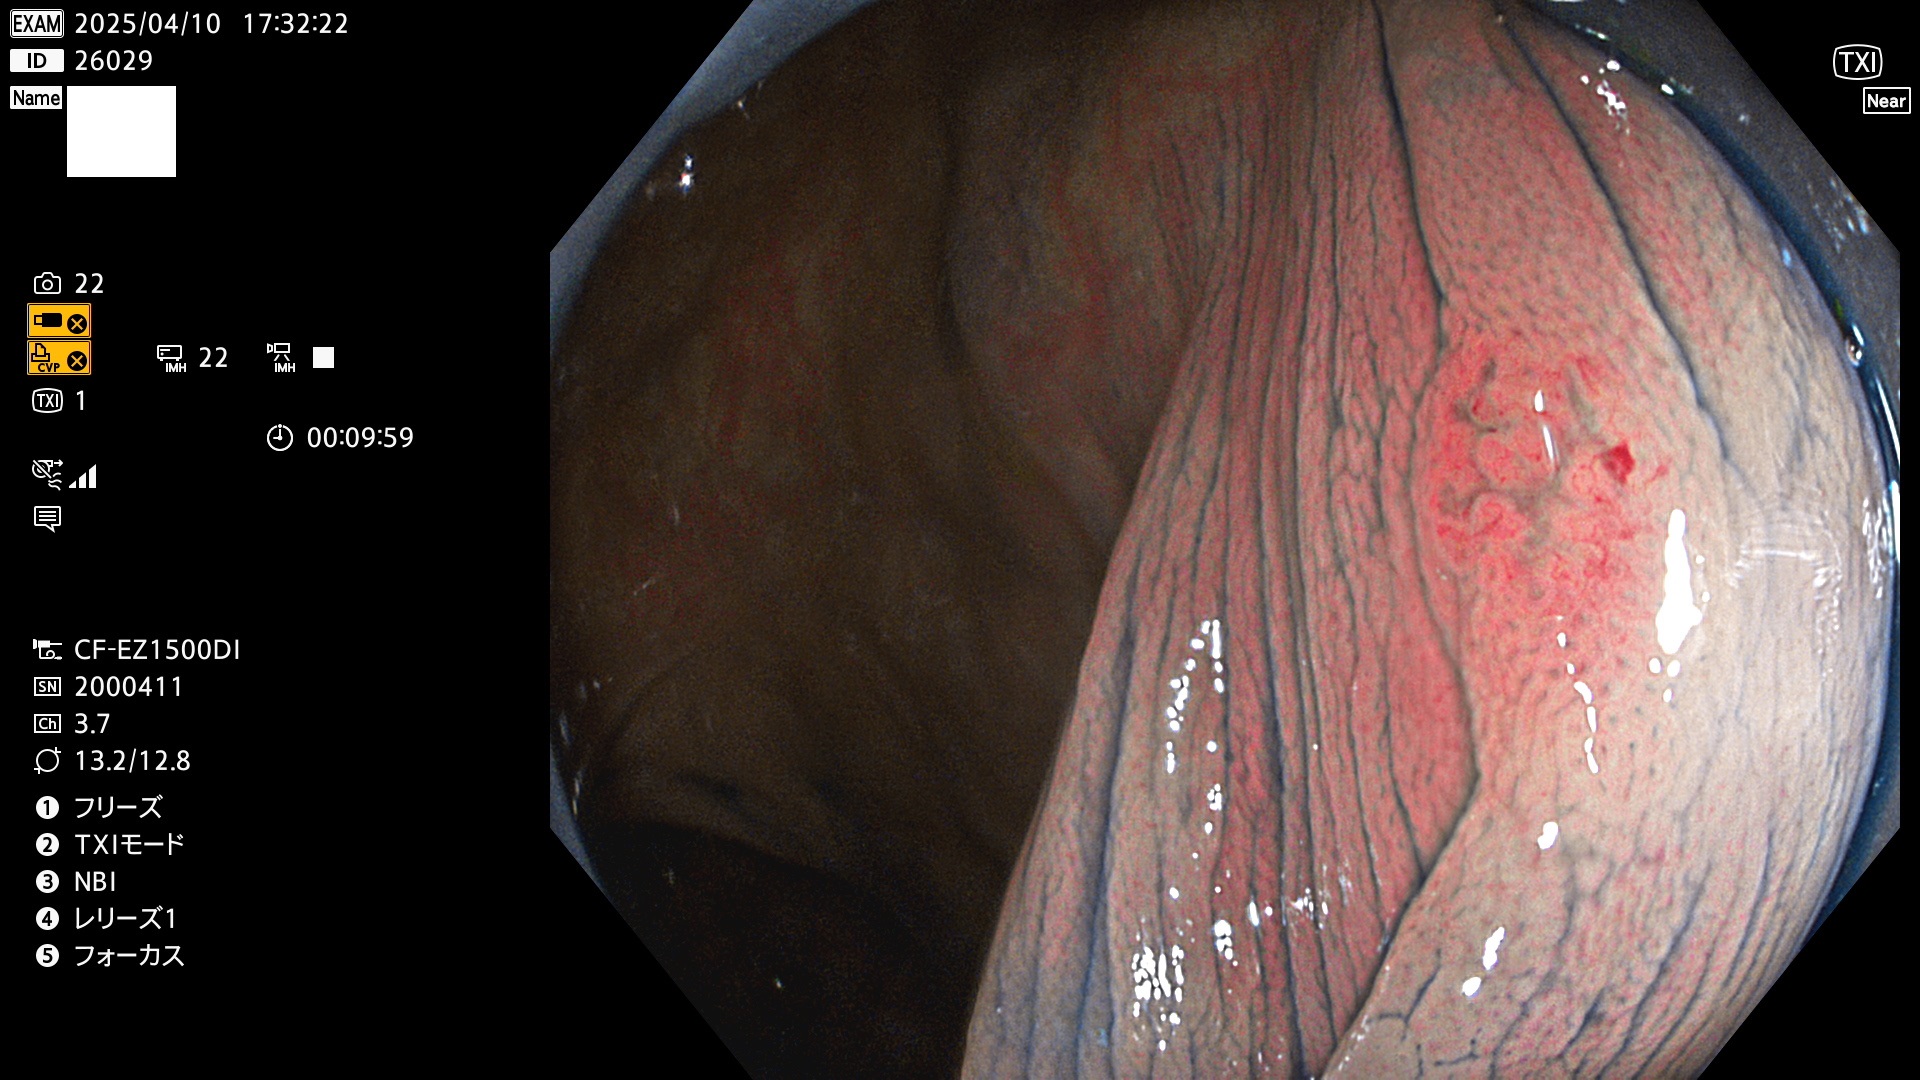

完全に平坦な物をUb、陥凹している物をUcと呼びます。Ubは認識が困難で、Ucはびらん(炎症)と紛らわしいために見落とされやすく、「内視鏡後・大腸癌」の原因になります。

抽出の対象期間 2025年4月10日〜4月13日の4日間(48件の検査)11個 (4/48=23%)

びらんと鑑別の困難なUc型腺腫